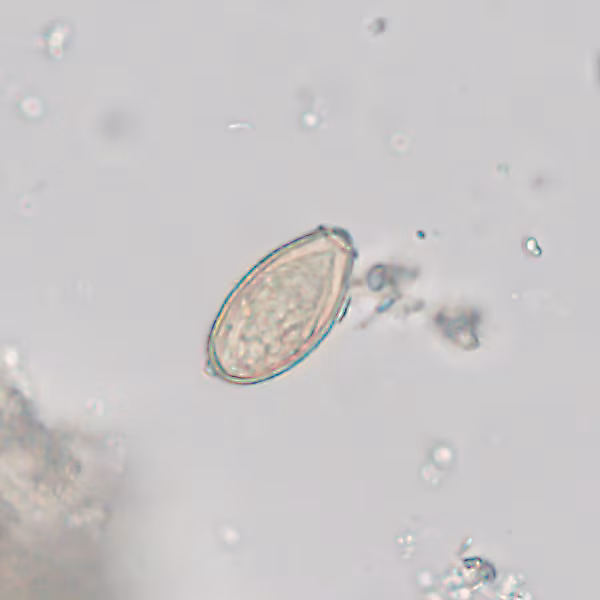

56-year-old Korean immigrant sought medical attention for non-specific abdominal pain and mild, intermittent diarrhea. A stool specimen was collected and sent for ova and parasite (O & P) examination. Figures A and B show what was detected in low numbers on a wet-mount preparation following fecal concentration. The objects of interest average 30 micrometers in length. What is your diagnosis? Based on what criteria?

Figure A